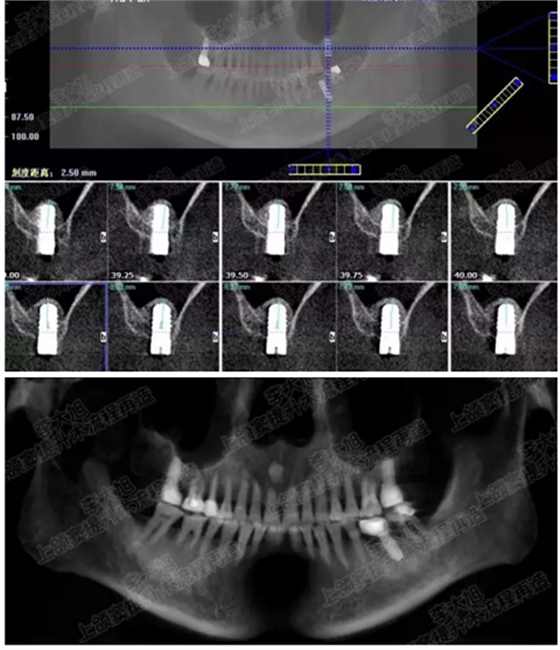

提升8mm

06.png

07.png

修復(fù)時(shí)根尖片

08.png

09.png

口內(nèi)照片

001.png

修復(fù)后一年

002.png